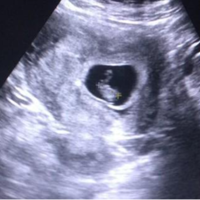

一般来说在怀孕后的前10周孕酮低都是最危险的,孕酮和绒毛膜促性腺激素是维持妊娠持续的重要激素,由于在孕早期的前10周以内胚胎本身质量不高,胚胎还没有形成,这个时间段内如果没有足够的孕酮,那么就可能会导致胎儿出现流产、生化妊娠、死胎等一些不良的后果。

孕酮在孕期的10周之前,都处于危险期,因为对于早孕妇女来说,前十周孕酮是维持胚胎发育的关键因素,当然如果出现了在第10周前孕酮低也不用过于担心,可以通过以下的这些方法拉提升孕酮: